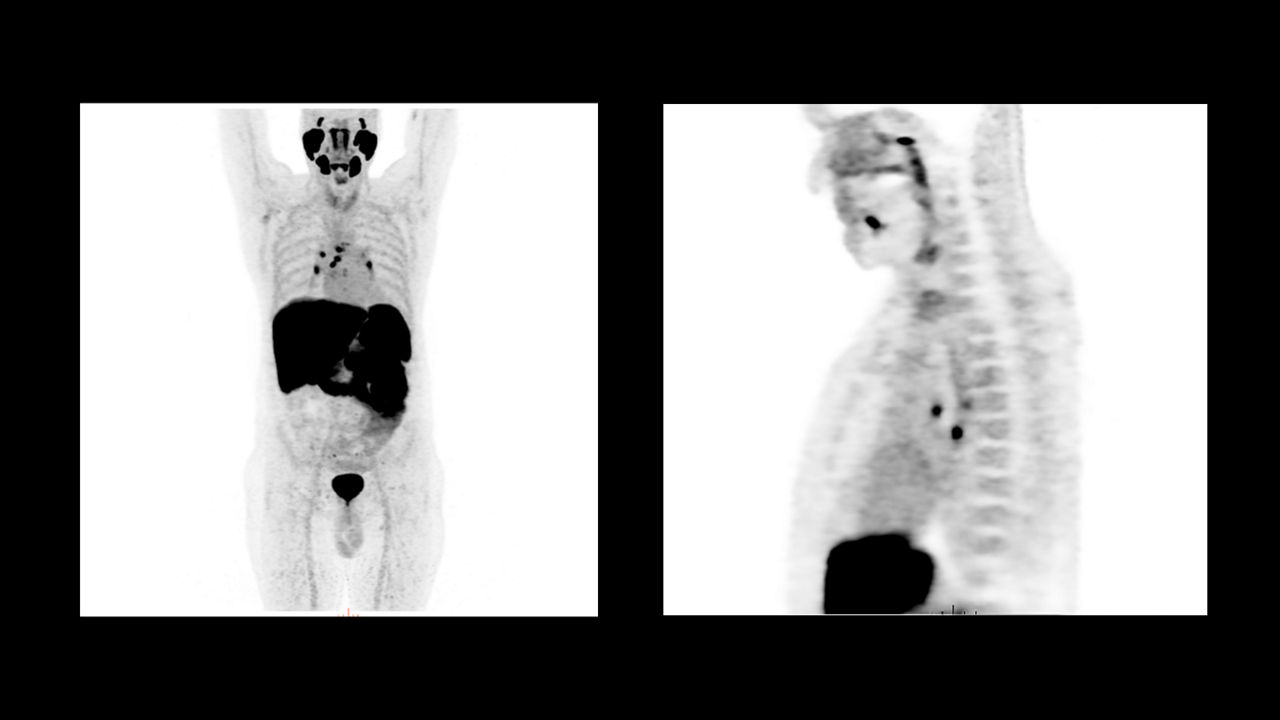

Seen here is a theranostics 18F-PSMA case, after prostate removal. There was suspected recurrence due to elevated markers. No pathological findings at the surgery area.

This image is a theranostics 68Ga-PSMA case for prostate cancer assessment response to treatment. There were pathological findings in the lymph nodes in the pelvic area.